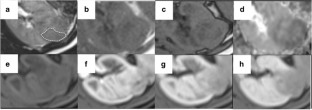

Fig. 2